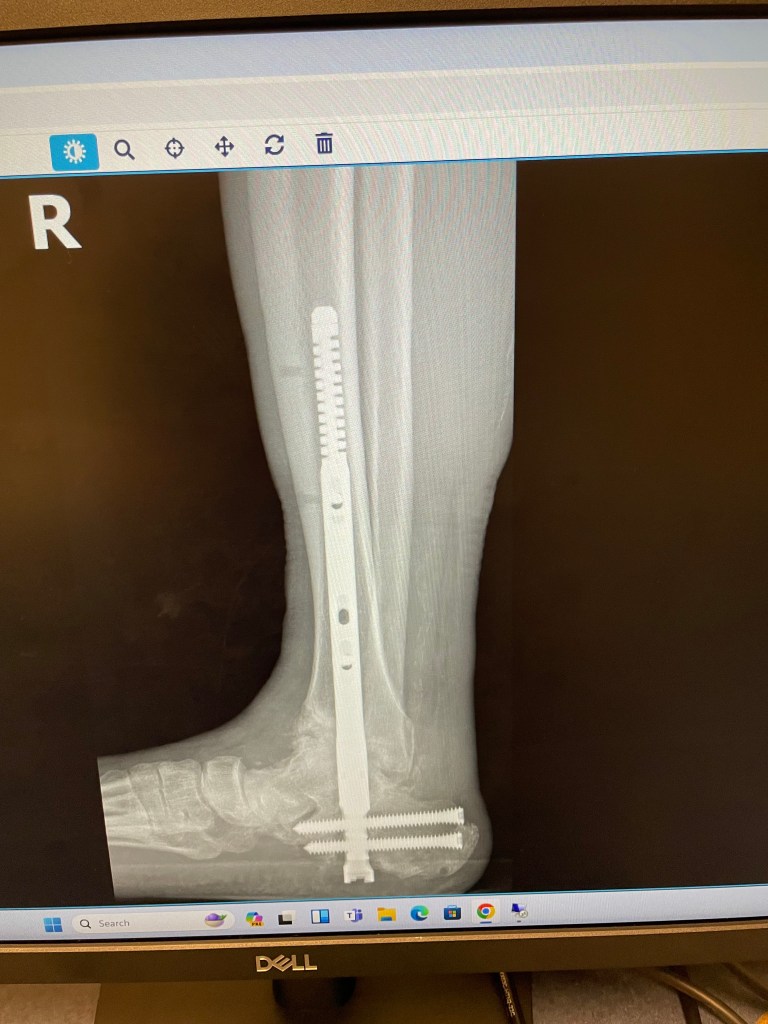

In case you do not know what external fixators are, they are exactly what the name says: external hardware to fix broken bones in place. Here is what I got last time.

You can see clearly that my ankle is dislocating downwards in the front. There is a growing hole right before you get to the toe bones. The problem was apparent on the May 13th x-ray, but much more obvious today. The other ankle surgeon at the office, a church friend, said that the bone is softer/weaker due to Charcot Foot, and usually that causes dislocations, fractures, and bone disintegration. By giving me another non-weight bearing cast, they hope to stabilize the ankle, and have it try to heal on its own.

Based on my luck so far, that is not likely. I will probably need more surgeries, including external fixators on the foot/ankle again. In the meantime, we are still waiting for another CT scan to get more clarity on what is happening.